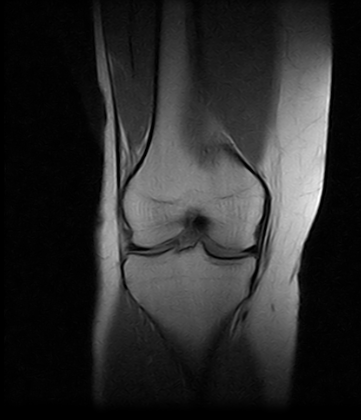

Ressonâncias Magnéticas Joelho

Se você pesquisa ressonâncias magnéticas joelho com eficiência e profissionalismo, não deixe de vir conhecer os serviços oferecidos pela RM Brasil.